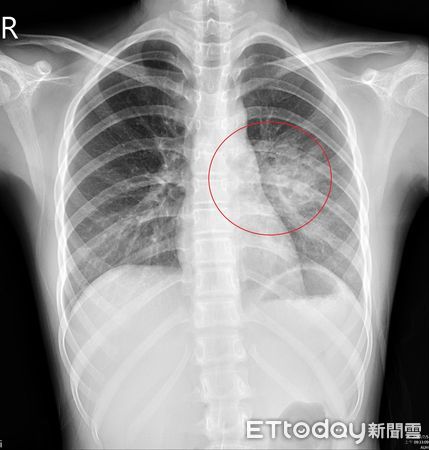

▲女童肺部竟有一顆3公分異常囊腫,多方確認後證實罹患罕見疾病「先天性肺氣道畸形」。(圖/亞大附醫提供)

12歲張姓女童日前因狂咳住院治療,期間反覆持續高燒,原本評估是黴漿菌引發肺炎,但就醫檢查後,醫師發現女童肺部竟有一顆3公分異常囊腫,多方確認後證實罹患罕見疾病「先天性肺氣道畸形」,採用微創胸腔鏡手術切除以降低囊腫癌化風險,術後女童恢復良好,家人才鬆了一口氣。

劉柏毅指出,這類肺部結構異常大多在懷孕中期就能透過例行檢查發現,然而也有部分病灶體積較小、症狀不明顯,直到孩童長大後,因其他疾病接受胸部影像檢查時才被意外發現,這次12歲女童就是因為住院期間安排X光檢查,兒科主任陳傑賀看報告時察覺「怪怪的」,經討論並反覆確認,才證實是CPAM肺部囊腫,家長讓女童接受微創手術後2天即出院,全家也計畫接下來要環島旅行。